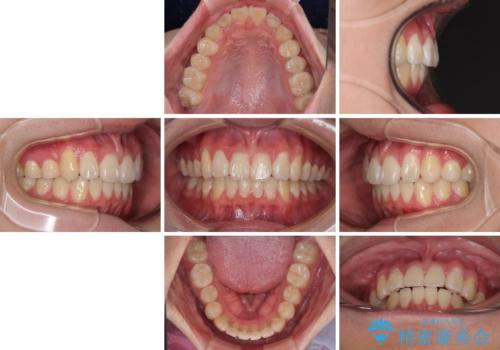

- 八重歯を気にして来院された高校生の患者様です。

ボディーコンタクトの激しい部活動を行っているため、補助装置とインビザラインを用いて、部活動を継続しながら治療を行うこととしました。

八重歯を効率よく改善するため、補助装置を使用して上顎の奥歯を後方に移動させました。

部活動をしながらでしたが、マウスピースをしっかりと装着してくださったので、1年半程度で終了することができました。